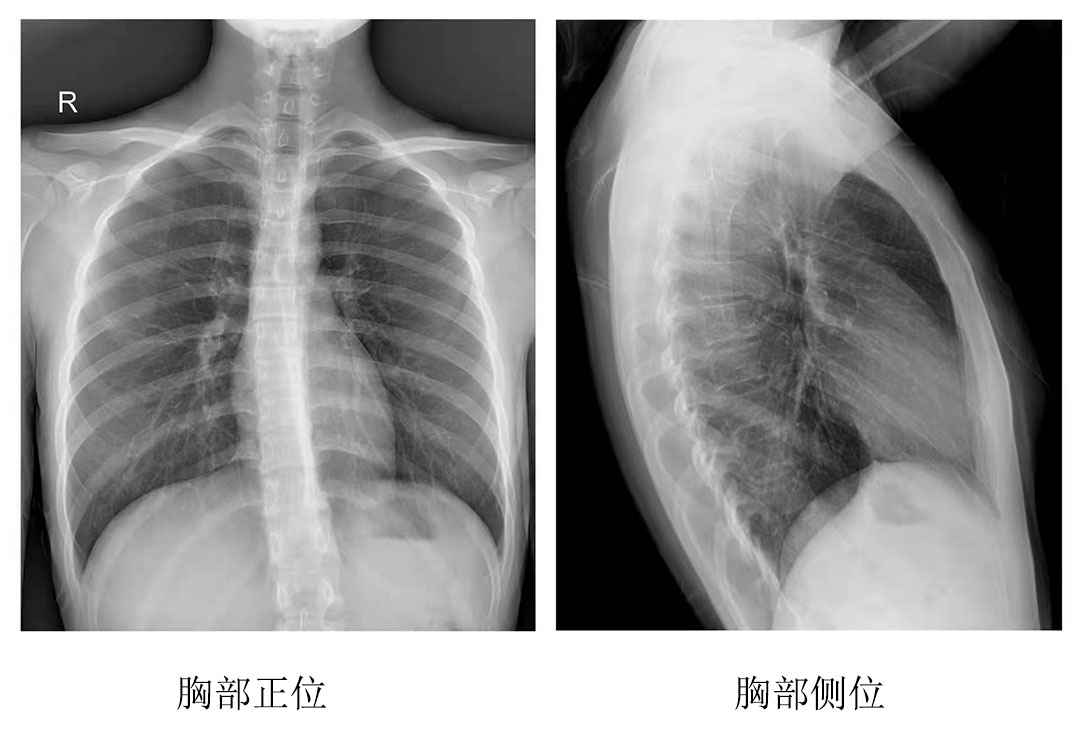

為其中一位年長(zhǎng)的患者完成拍片工作后,操作醫(yī)師表示:今天為這位年長(zhǎng)的患者服務(wù)時(shí),動(dòng)態(tài)平板DRF的床體升降和腳踏板360度旋轉(zhuǎn)功能很實(shí)用,上下床非常方便。不但減輕醫(yī)護(hù)人員的負(fù)擔(dān),也縮短了患者的檢查時(shí)間,拍出來的圖像很清晰,對(duì)拍片成果很滿意。